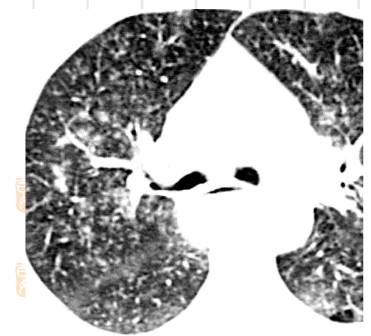

结核,高分辨率CT显示右肺周围边界不清,大小不等,这些征象代表了支气管内结核的播散